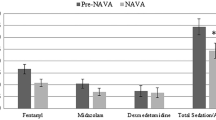

All patients were intubated with a cuffed endotracheal tube (Mallinckrodt Medical, Westmeath, Ireland). General anesthesia was maintained with inhaled sevoflurane, intravenous fentanyl, and pancuronium bromide. CPB with modified ultrafiltration was performed for 56–120 min (median 98 min) without aortic cross-clamping in 22 patients (Table 1) as the routine strategy in our institution, while another patient underwent the BCPA procedure without CPB. All patients were weaned from CPB when the transesophageal temperature reached 35 °C and hemodynamic stability was achieved. On return to the cardiac intensive care unit, patients were mechanically ventilated with a Servo-i ventilator (Maquet Critical Care, Solna, Sweden) capable of delivering PCV, PSV, and NAVA. The FiO2 was 0.40–0.60 in all patients. The aim of mechanical ventilation was to maintain PaCO2 at 40 mmHg and PaO2 ≥40 mmHg. Rectal temperature was maintained at 36–37.5 °C using a cooling or warming blanket. The patients received infusions of propofol (2 mg/kg/h) for the duration of the study. Hemoglobin concentration was maintained at or above 120 g/L. Dopamine (5 mcg/kg/min) and milrinone (0.5 mcg/kg/min) were infused to maintain hemodynamic stability. Superior vena cava pressure was monitored and maintained between 10–20 mmHg by infusion of 5 % albumin (5 mL/kg) before the start of the study. After stabilization, the insertion and correct positioning of the EAdi catheter were assured by means of a specific function in the ventilator (“EAdi catheter positioning”). Inotropes, vasodilators, PEEP, and FiO2 were not adjusted after study initiation.

The study protocol was started within 2 h of discontinuation of CPB and as soon as a cardiorespiratory steady state was achieved. The protocol consisted of two periods, which were defined as control ventilation and assist ventilation. FiO2 was fixed at 0.4 for all patients after study initiation. PEEP, routinely set at 3–4 cmH2O, was maintained constant throughout the study period. During the first period of the study, all subjects were ventilated with PCV titrated to achieve a tidal volume (V T) of 10 mL/kg (PCVlow) or 15 mL/kg (PCVhigh) at the same respiratory frequency for 30 min with a close monitor of ventilator pressure and hemodynamic in a random order before awake from anesthesia. If hemodynamic instability of patient or the peak inspiratory pressure was more than 20 cmH2O, he will be withdrawn from the study immediately. When the first period was finished and signs of EAdi recovery were registered, the second study period was initiated. EAdi level after 2 min of continuous positive airway pressure was considered EAdibase. After establishing EAdibase, administration of two levels of PSV and NAVA was initiated, following a predefined computer-generated random sequence, defined as levellow and levelhigh. Respiratory assist was delivered to achieve a reduction in peak EAdi by 50 % of EAdibase (PSVlow) and (NAVAlow). During levelhigh, respiratory assist was administered to achieve a reduction in peak EAdi by 75 % of EAdibase (PSVhigh) and (NAVAhigh). Each patient underwent four 30-min trials during the second period. The last 5 min of each trial was recorded and stored on a dedicated personal computer for data analysis. The systolic peak velocity (V s) and the end diastolic velocity (V d) of MCABF measured by TCD were recorded during the last 2 min of each trial. The mean velocity (V m) of MCABF was calculated as “V m = (V s − V d)/3 + V d.” The pulsatility index (PI) was calculated as “PI = (V s − V d)/V m.” At the end of each test period, an arterial blood sample was collected for blood gas analysis.

We did not distinguish between the effects of hypercarbia and intrathoracic pressure on CBF and PBF. These two factors are difficult to separate and represent the combined influence of the factors of oxygenation in BCPA circulation. Time considerations did not allow this project to separate the differences related to hypercarbia and intrathoracic pressure, and our results are not objective. We only compared NAVA and PSV in our study, without involving other ventilation strategies. And 30 min of ventilation might be limited in patients with other interfering factors to reach steady state. Further research needs to be done in the future. Some authors reported that CBF was influenced by a high concentration of sedatives [31, 32]. However, the dose of propofol maintained in our study was small and identical in all patients. Thus, the influence of sedatives on MCABF velocity in our study was probably limited.